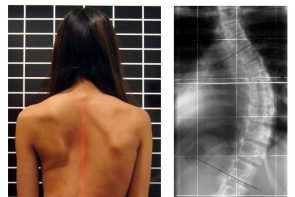

Ginnastica preventiva e correttiva

I nostri specialisti ti guideranno nella risoluzione dei più comuni problemi di postura e ti aiuteranno a ritrovare una perfetta forma fisica in linea con la tua salute.

Ginnastica posturale

Ginnastica correttiva